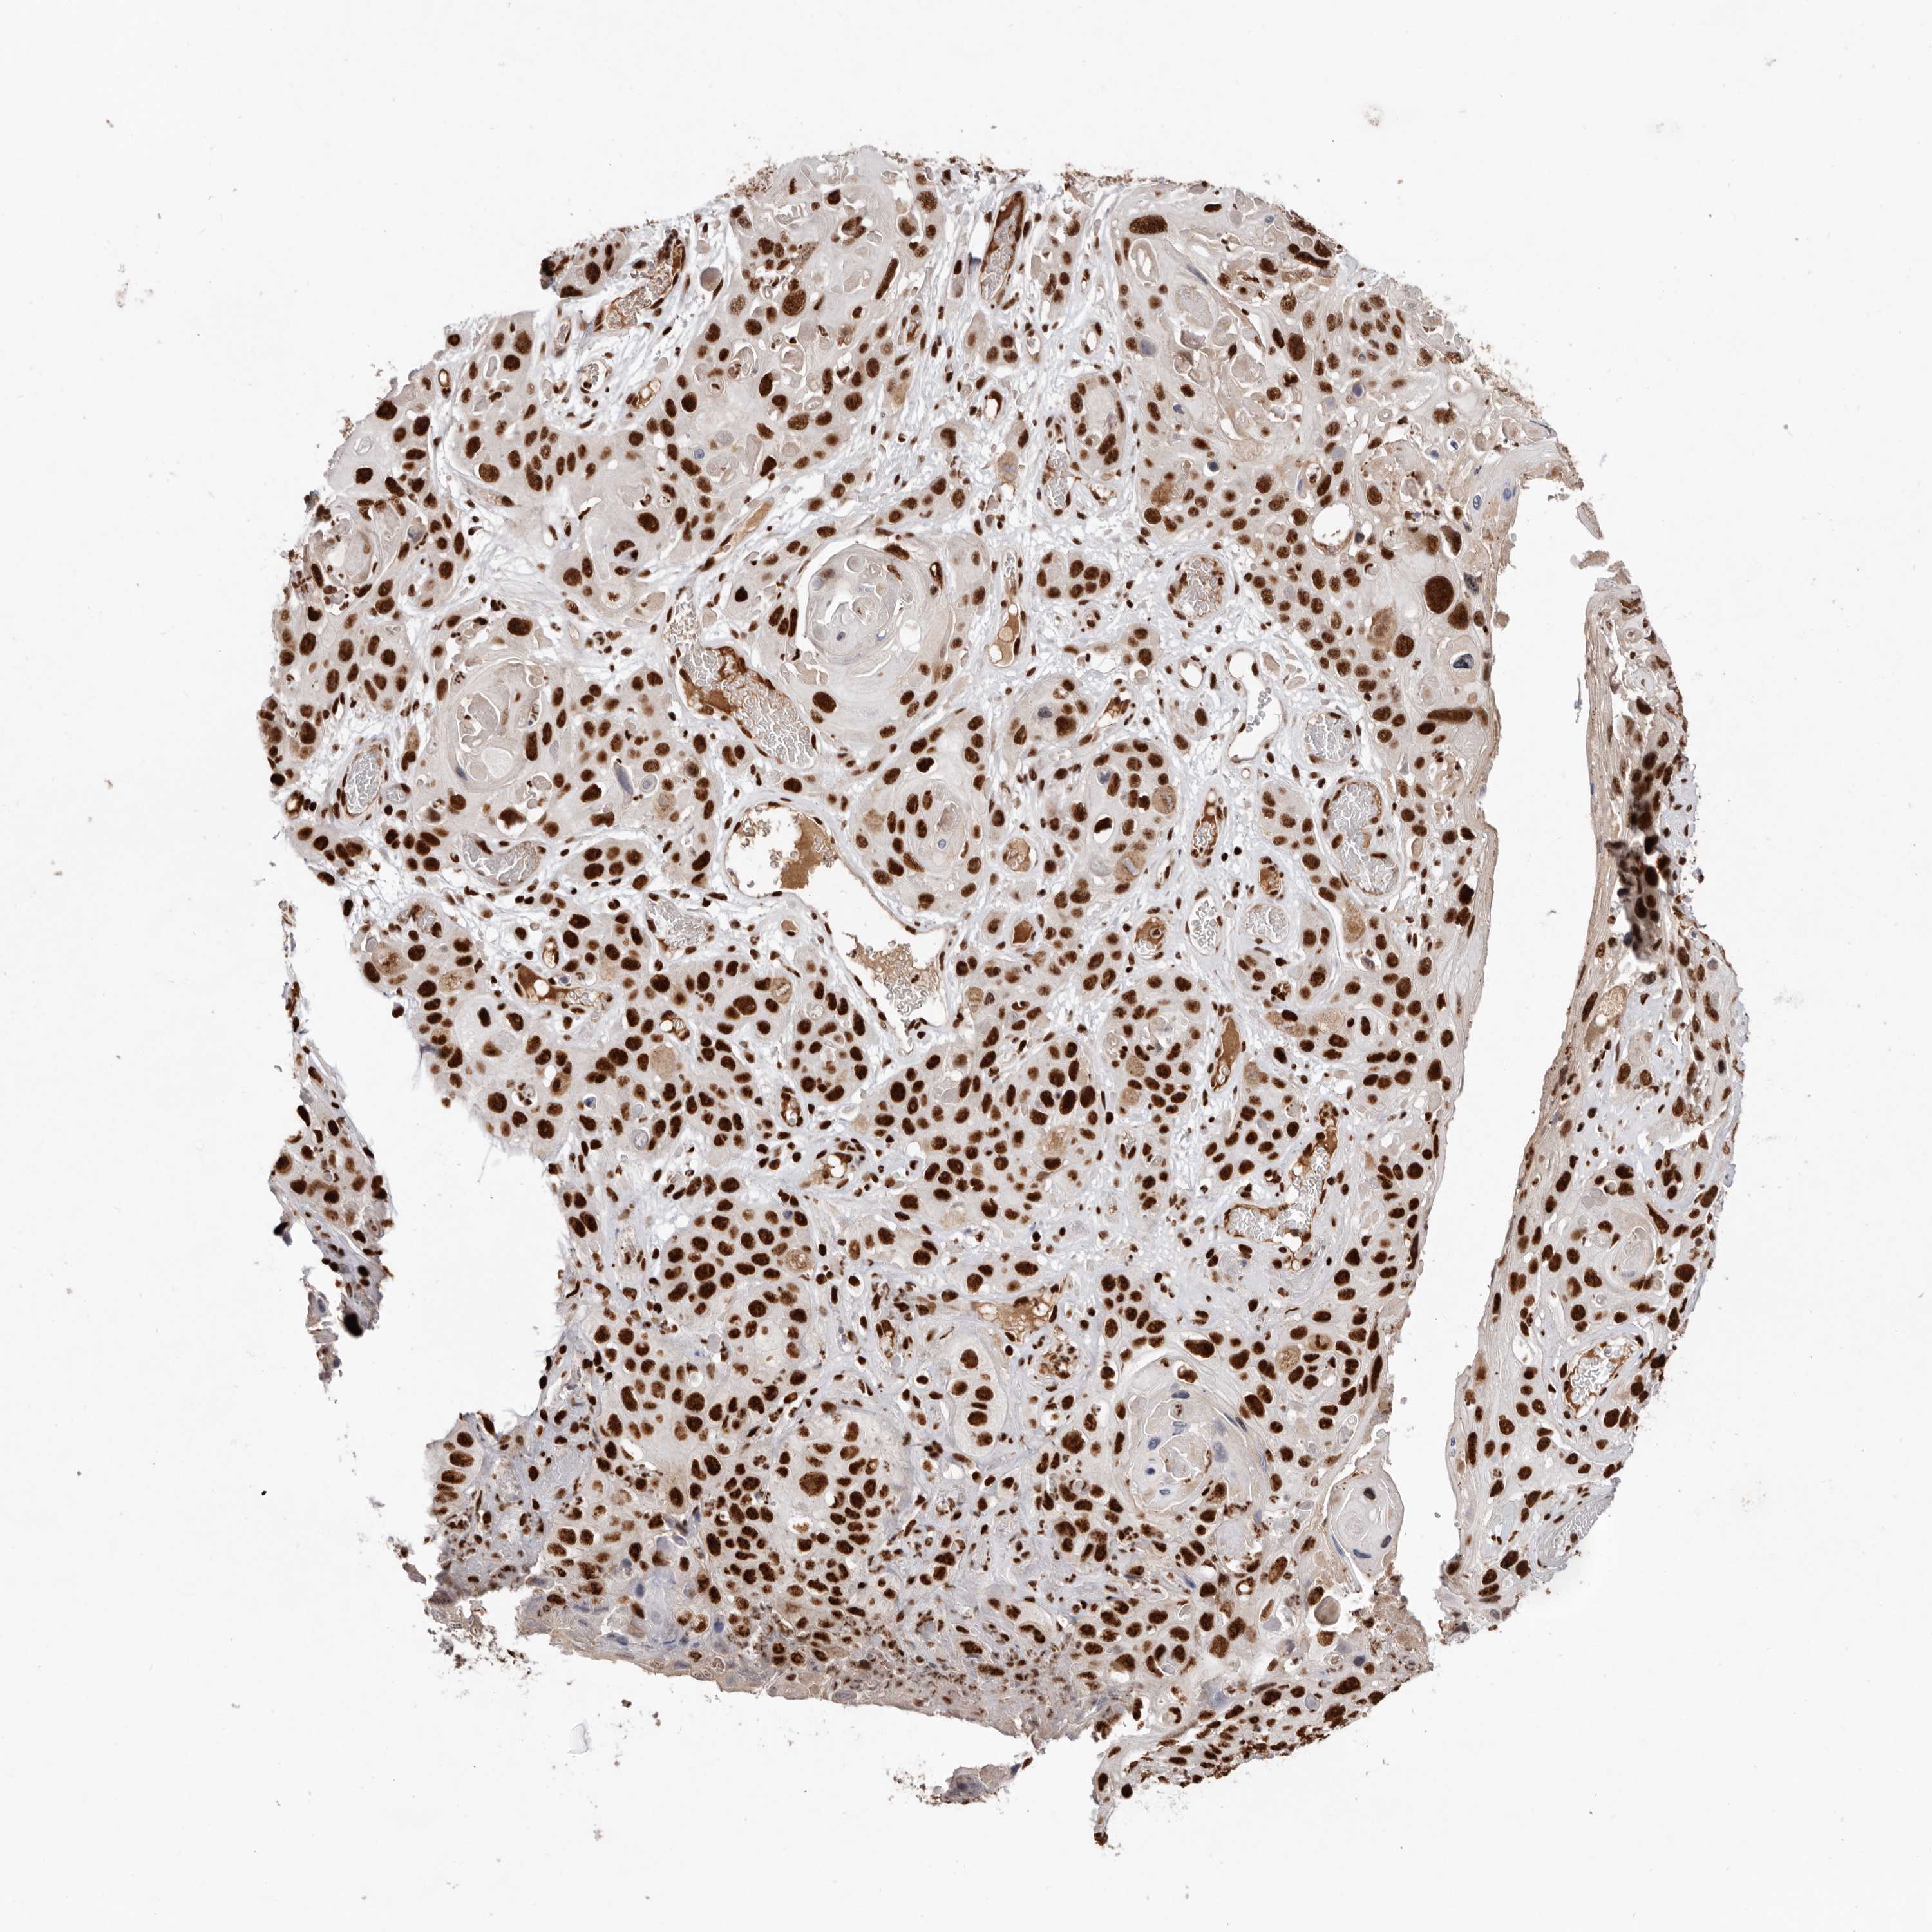

Antibody HPA028647

Staining

Medium

Intensity

Moderate

Quantity

75%-25%

Location

Nuclear

Squamous cell carcinoma, NOS